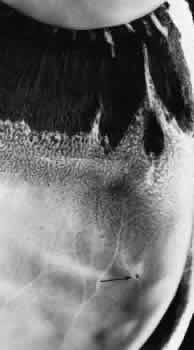

PERIPHERAL RETINAL EXCAVATION

Peripheral retinal excavation appears as a rather small oval depression in the retina. Usually this lesion is aligned meridionally with a meridional fold or complex and located 1 to 7.2 mm posterior to the ora serrata (Fig. 13; see Figs. 6 and 12). The focal depression may be surrounded by margins that appear to be elevated; however, microscopic examination reveals that the depression corresponds to afocal loss of the inner retinal layers and that the surrounding tissue is normal (Fig. 14).

Fig. 13. Meridional complexes with peripheral retinal excavation. Two complexes can be seen anteriorly; both contain meridional folds (the fold of complex on the right is discontinuous). Peripheral retinal excavation (arrow) is aligned with the complex on the left (× 12.)

Peripheral retinal excavation is present in 10% of patients, is bilateral in 43%, and therefore is evident in 8% of all eyes (see Table 2). Half of the affected eyes contain two or more areas of focal excavation, and most of the excavations are located in the superior nasal quadrant.